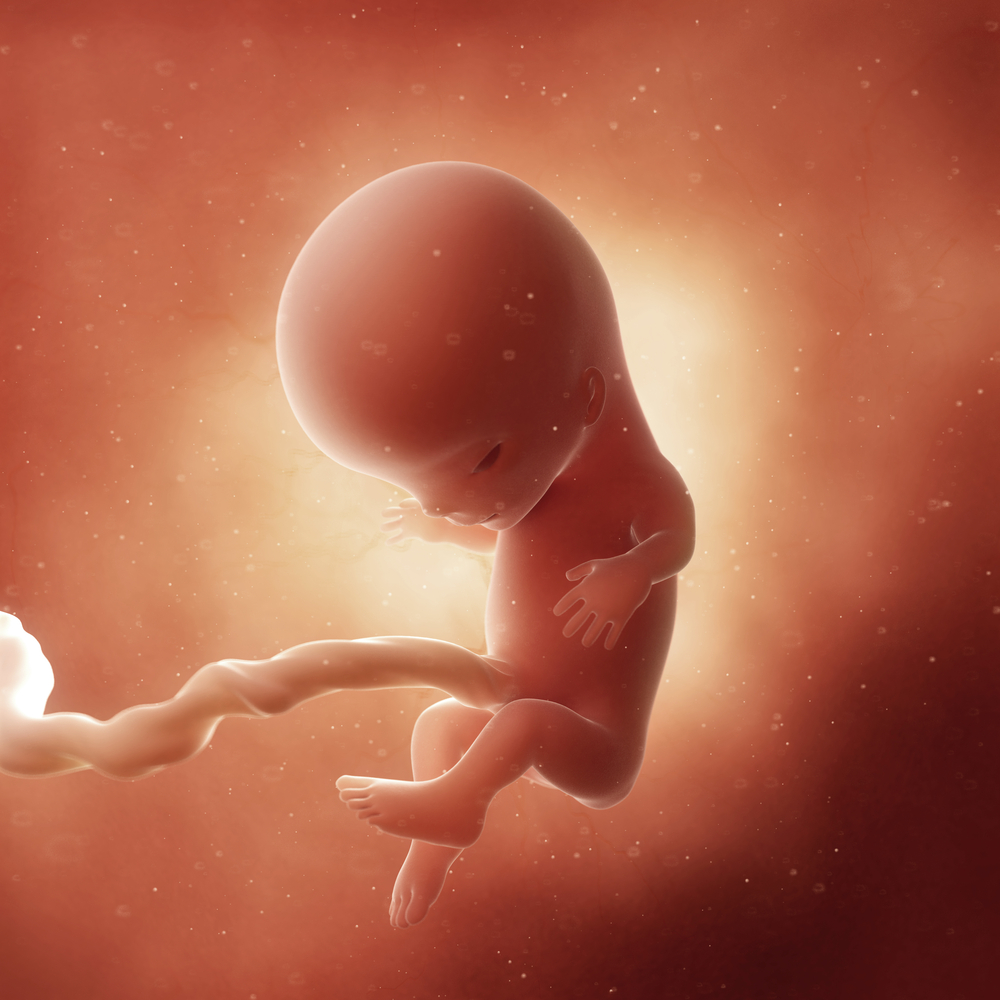

Зародыш ребенка 10 недель

Зародыш на 10 неделе беременности

Зародыш человека 9-10 недель

Человеческий эмбрион 10 недель